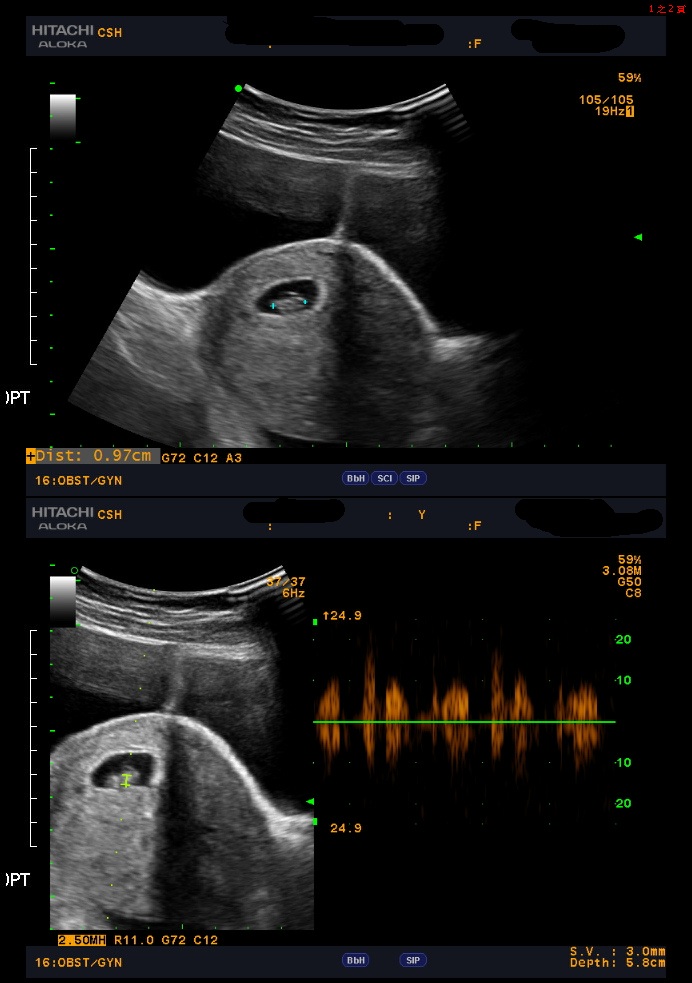

MIRA找出妳的植入時程 2023-12-28

婚後懷孕未果 著床時間異於常人

夫妻婚後未孕且AMH值低,利用MIRA檢測子宮內膜狀態,發現著床時間異於常人,調整後成功生下女寶寶。祝福新手爸媽